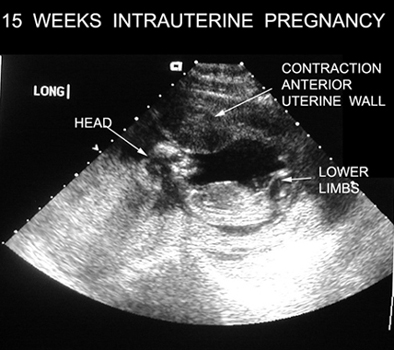

15 Weeks Intrauterine Pregnancy |

|